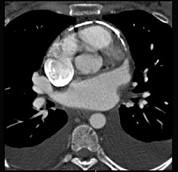

男性45岁,心悸气促乏力,下肢肿胀半年余,曾患肺结核,胸部CT扫描如图所示,请选择正确的选项为 ( )A、X线、CT为常用检查方法B、...

相关内容:男性,气促,下肢,半年,曾患,肺结核,胸部,扫描,如图,选项,常用,检查,方法